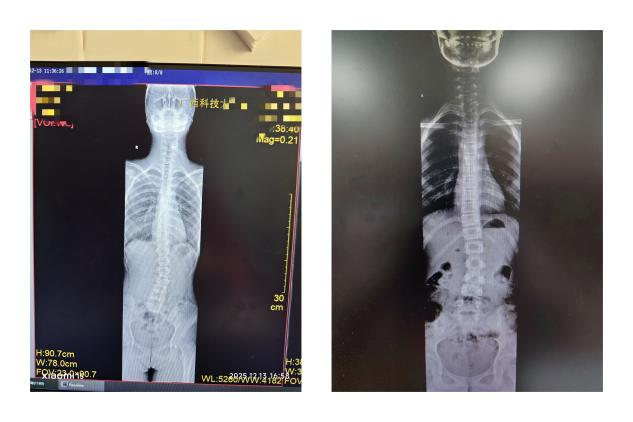

1. 青少年特发性脊柱侧弯: